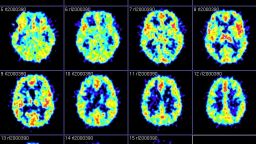

Animal studies allow neuroscientists to study the brain at the level of individual neurons, unlike human brain-imaging studies.